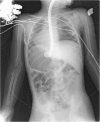

Case presentation: A 3-year-old Caucasian girl presented to the emergency room of a community hospital complaining of abdominal pain. An abdominal X-ray showed a coin lithium battery located in the fundus of her stomach, and she was transferred to a referral pediatric hospital. In the following hours she developed massive hematemesis and severe hypovolemic shock. An emergency laparotomy was attempted, and the coin battery was removed. The initial surgery and multiple blood transfusions did not, however, improve the clinical situation. She was then referred to our tertiary referral center, where a multidisciplinary team decided to attempt a combined angiographic and endoscopic approach to resolve a life-threatening aortoesophageal fistula. A 3-year follow-up was uneventful.